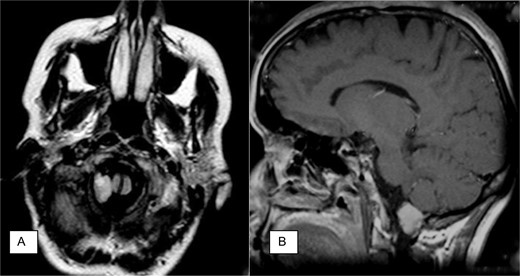

The MRI showed a gadolinium-enhanced extra-axial mass within the right aspect of the foramen magnum. The mass extended from the medulla oblongata to the C1 level of the spinal cord, deforming the right aspect of the upper cervical spinal cord and medulla oblongata. The MRI was complemented by a CT scan and by dynamic cervical spinal X-ray (flexion–extension views; Fig. 1 ).

Neuroradiology findings. (A) Axial fast fluid-attenuated inversion recovery (FLAIR) image demonstrates intradural mass at the right foramen magnum resulting in slight displacement of the medulla and transdural hypoglossal canal involvement. (B) Sagittal contrast-enhanced T1-weighted spin-echo image demonstrates intradural mass at foramen magnum.